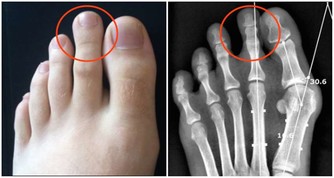

牙齒鬆動——凡是牙齒鬆動,都應考慮腎虛的可能。腎主骨,骨靠腎精滋養,腎好骨才好。而齒為骨之餘,骨頭的好壞直接影響到牙齒的好壞。所以,腎與牙齒有著密切關係,腎虛則骨失所養,牙齒就會不堅固,出現牙齒鬆動的問題。